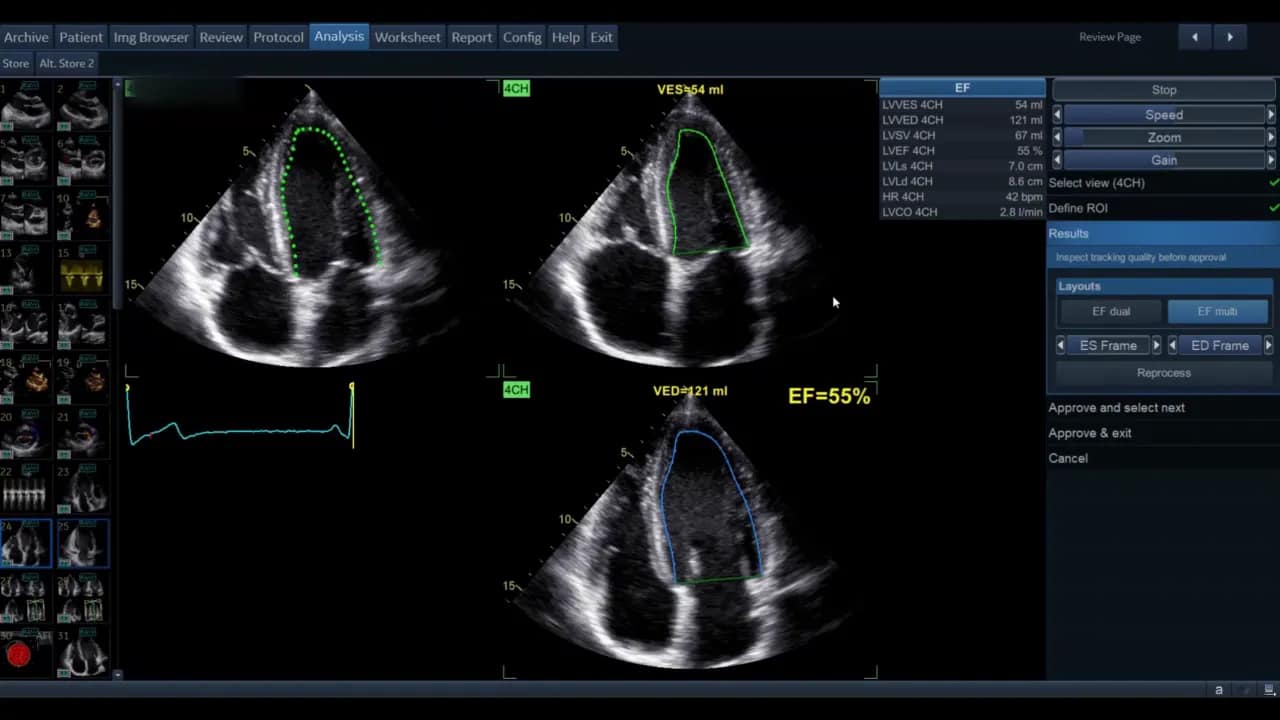

Die Ansicht kann als Einzelbild oder als EF‑Dual‑Display gezeigt werden. Im Dual‑Display sehen Sie gleichzeitig Systole und Diastole mit den berechneten Volumina und der Ejektionsfraktion als Prozentsatz.

Die Software zeigt nach erfolgreichem Durchlauf die systolischen und diastolischen Volumina beider Ansichten sowie die berechnete biplane Ejektionsfraktion. Diese Werte erscheinen in der Ergebnisliste; die biplane EF wird in der Regel als kombinierter Wert ausgewiesen.

Wenn Sie zufrieden sind, wählen Sie Approve and Exit. Die Messwerte werden in das Arbeitsblatt bzw. in die Messliste übernommen. Wollen Sie die Ergebnisse verwerfen, wählen Sie Cancel.